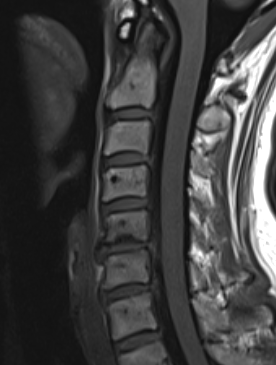

MRI

Degenerative disc changes

- dessication (loss of fluid)

- narrowing

- end plate changes

End plate changes Disc dessication with disc bulge